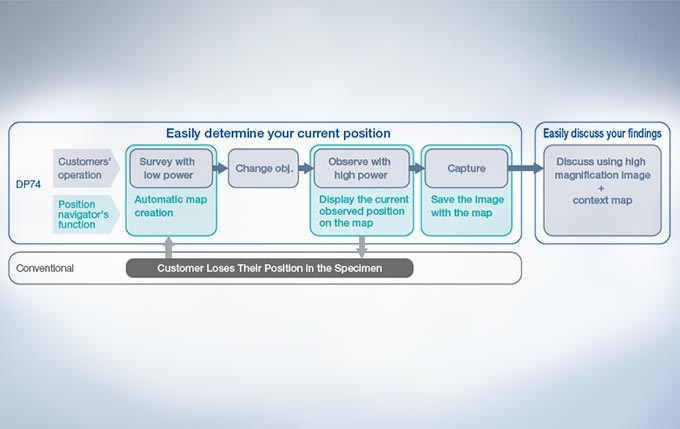

Easily know the location of interest with the Position Navigator

The position navigator adds convenience to the operator’s workflow because it creates a map to help users keep track of their location within the specimen; this is especially useful when making observations at high magnification. This is achieved without the need for a motorized or encoded stage. The low-magnification map of the sample containing all of the pertinent location information can be stored along with the high-magnification observation image, making it convenient for record keeping or creating presentation materials. *The accuracy of the map creation and the position navigation depends on observed samples...

Context Map And High-Magnification Images Stored in a Single File

The metadata images used in the camera’s mapping feature can also be used as stand-alone images. In addition, the entire overview map and high-magnification image can be saved and exported in a common file format for enhanced flexibility. Users are able to place markers in real-time on the overview map to highlight potential areas of interest, making it easy to go back and re-image previously viewed areas.